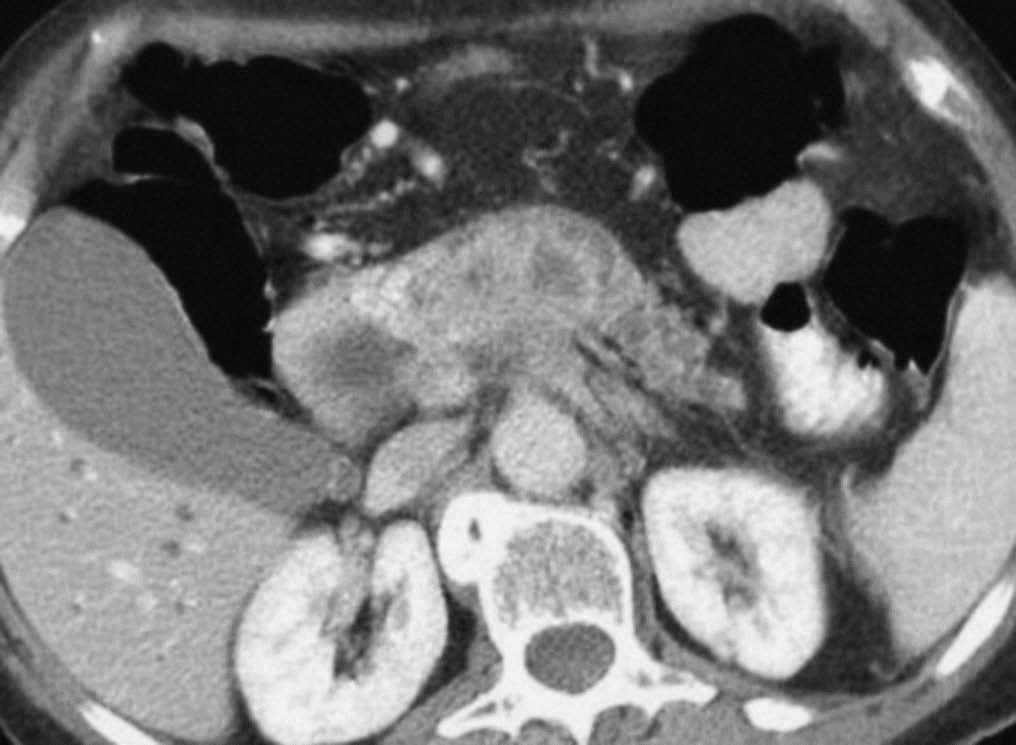

Varias cadenas ganglionares drenan el páncreas. La cabeza de la glándula drena hacia la cadena del surco pancreaticoduodenal y a través de ella, en los grupos ganglionares subpilórico, portal, mesocólico, mesentérico y aortocaval. El cuerpo y cola pancreáticos drenan hacia los grupos ganglionares retroperitoneales, hacia el hilio esplénico, o bien hacia los ganglios de la cadena celíaca, aortocaval, mesocólica o mesentérica. La mayoría de estudios valoran como metastáticas las adenopatías que miden más de 1 cm en su eje corto, no obstante ganglios de tamaño normal pueden contener micrometástasis, mientras que ganglios aumentados de tamaño pueden ser reactivos (fig. 9). Esto supone una importante limitación para la TC que evalúa únicamente en función de parámetros anatómicos. No obstante, como los ganglios regionales a menudo pueden ser resecados en la cirugía no representan una contraindicación quirúrgica formal.

Fig. 9.--Tomografía computarizada en fase pancreatográfica en un paciente con neoplasia de cabeza pancreática que muestra adenopatías de 15 mm de diámetro máximo en región celíaca (puntas de flechas) que resultaron ser reactivas en el estudio anatomopatológico.